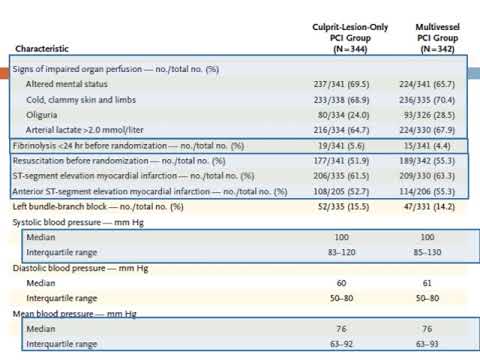

Angioplastia en el shock cardiogénico post IAM. Dra. Sofía Gabriela Rodríguez. Residencia de Cardiología. Hospital C. Argerich. Buenos Aires